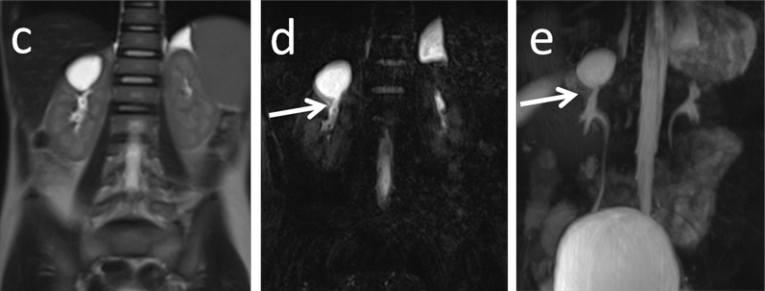

3、磁共振主要表现为:T2 高信号,可以看到细小的裂隙与肾盏相通,在 MRU 上更为清晰;

磁共振 T2 序列于 MRU 成像上可以看到囊腔与肾盏相通

磁共振增强上可以看到造影剂进入囊腔内;